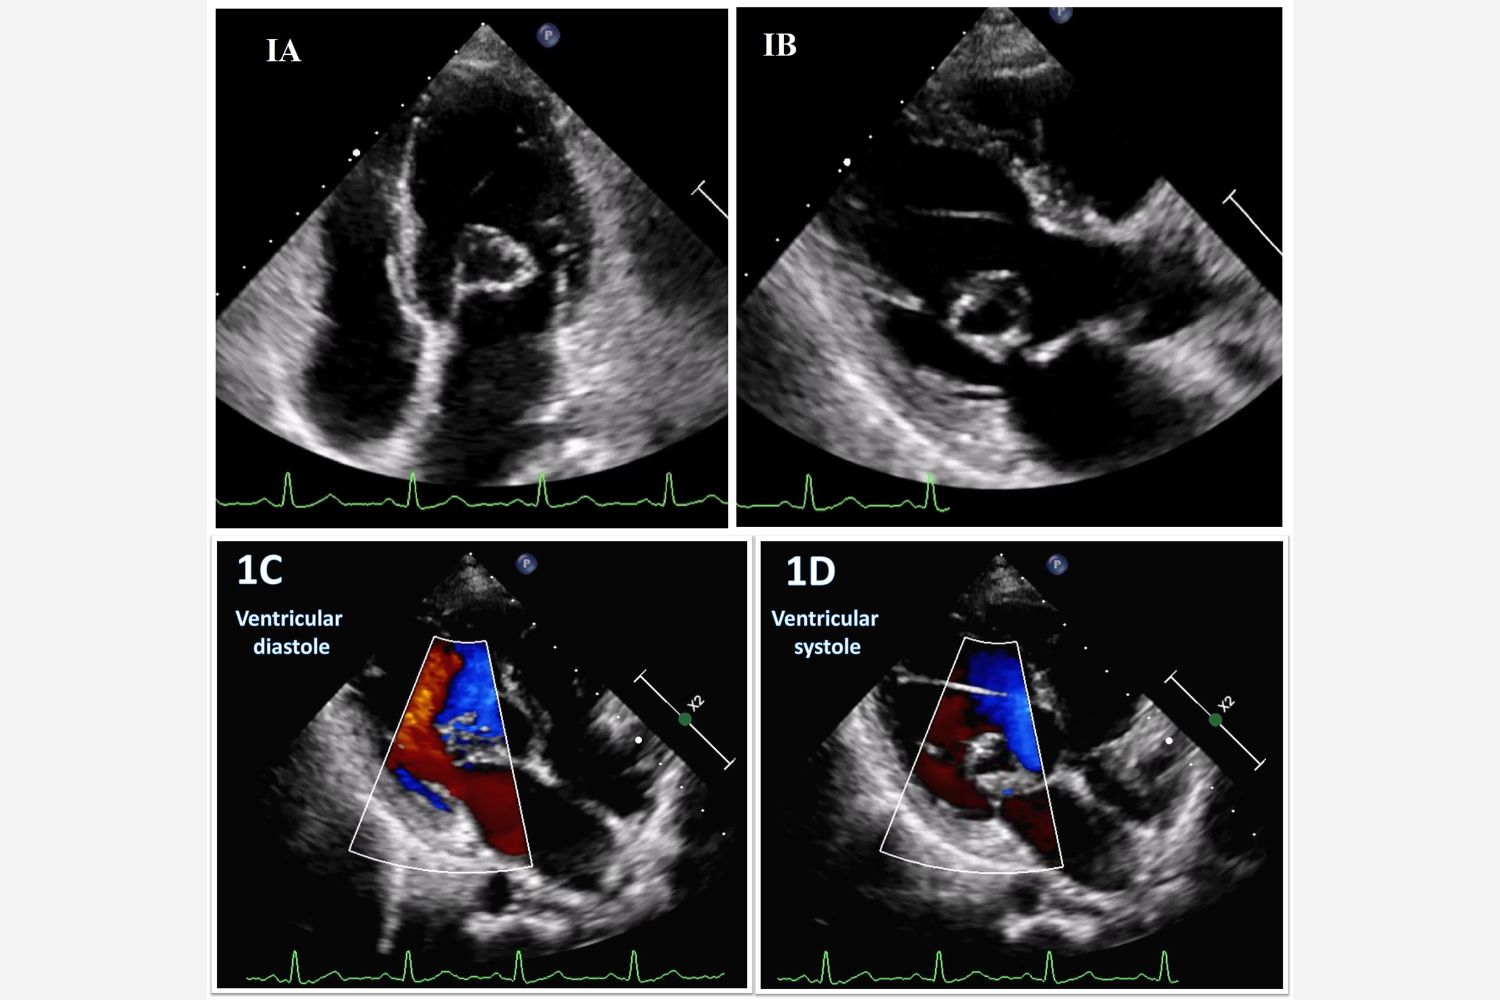

Image of the Week - 14 May 2025

13 May 2025

Image of the week